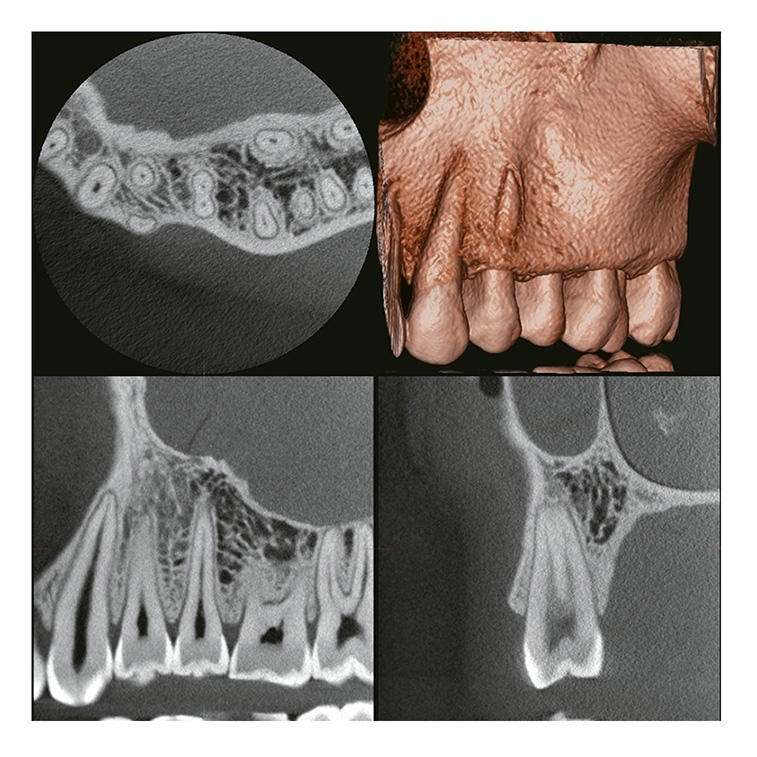

2 VERAVIEW (X800) CP (S) / (M) / (L)

Panoramique/Céphalostat 3D & 2D

FOV Jusqu'à: Ø 150 X H 140